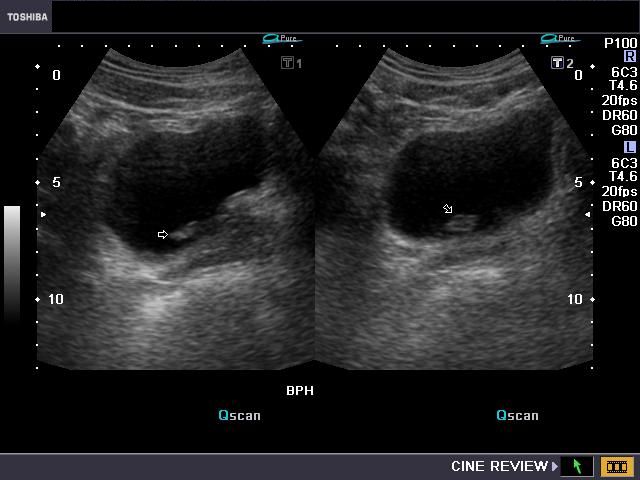

POLYP ULTRASOUND